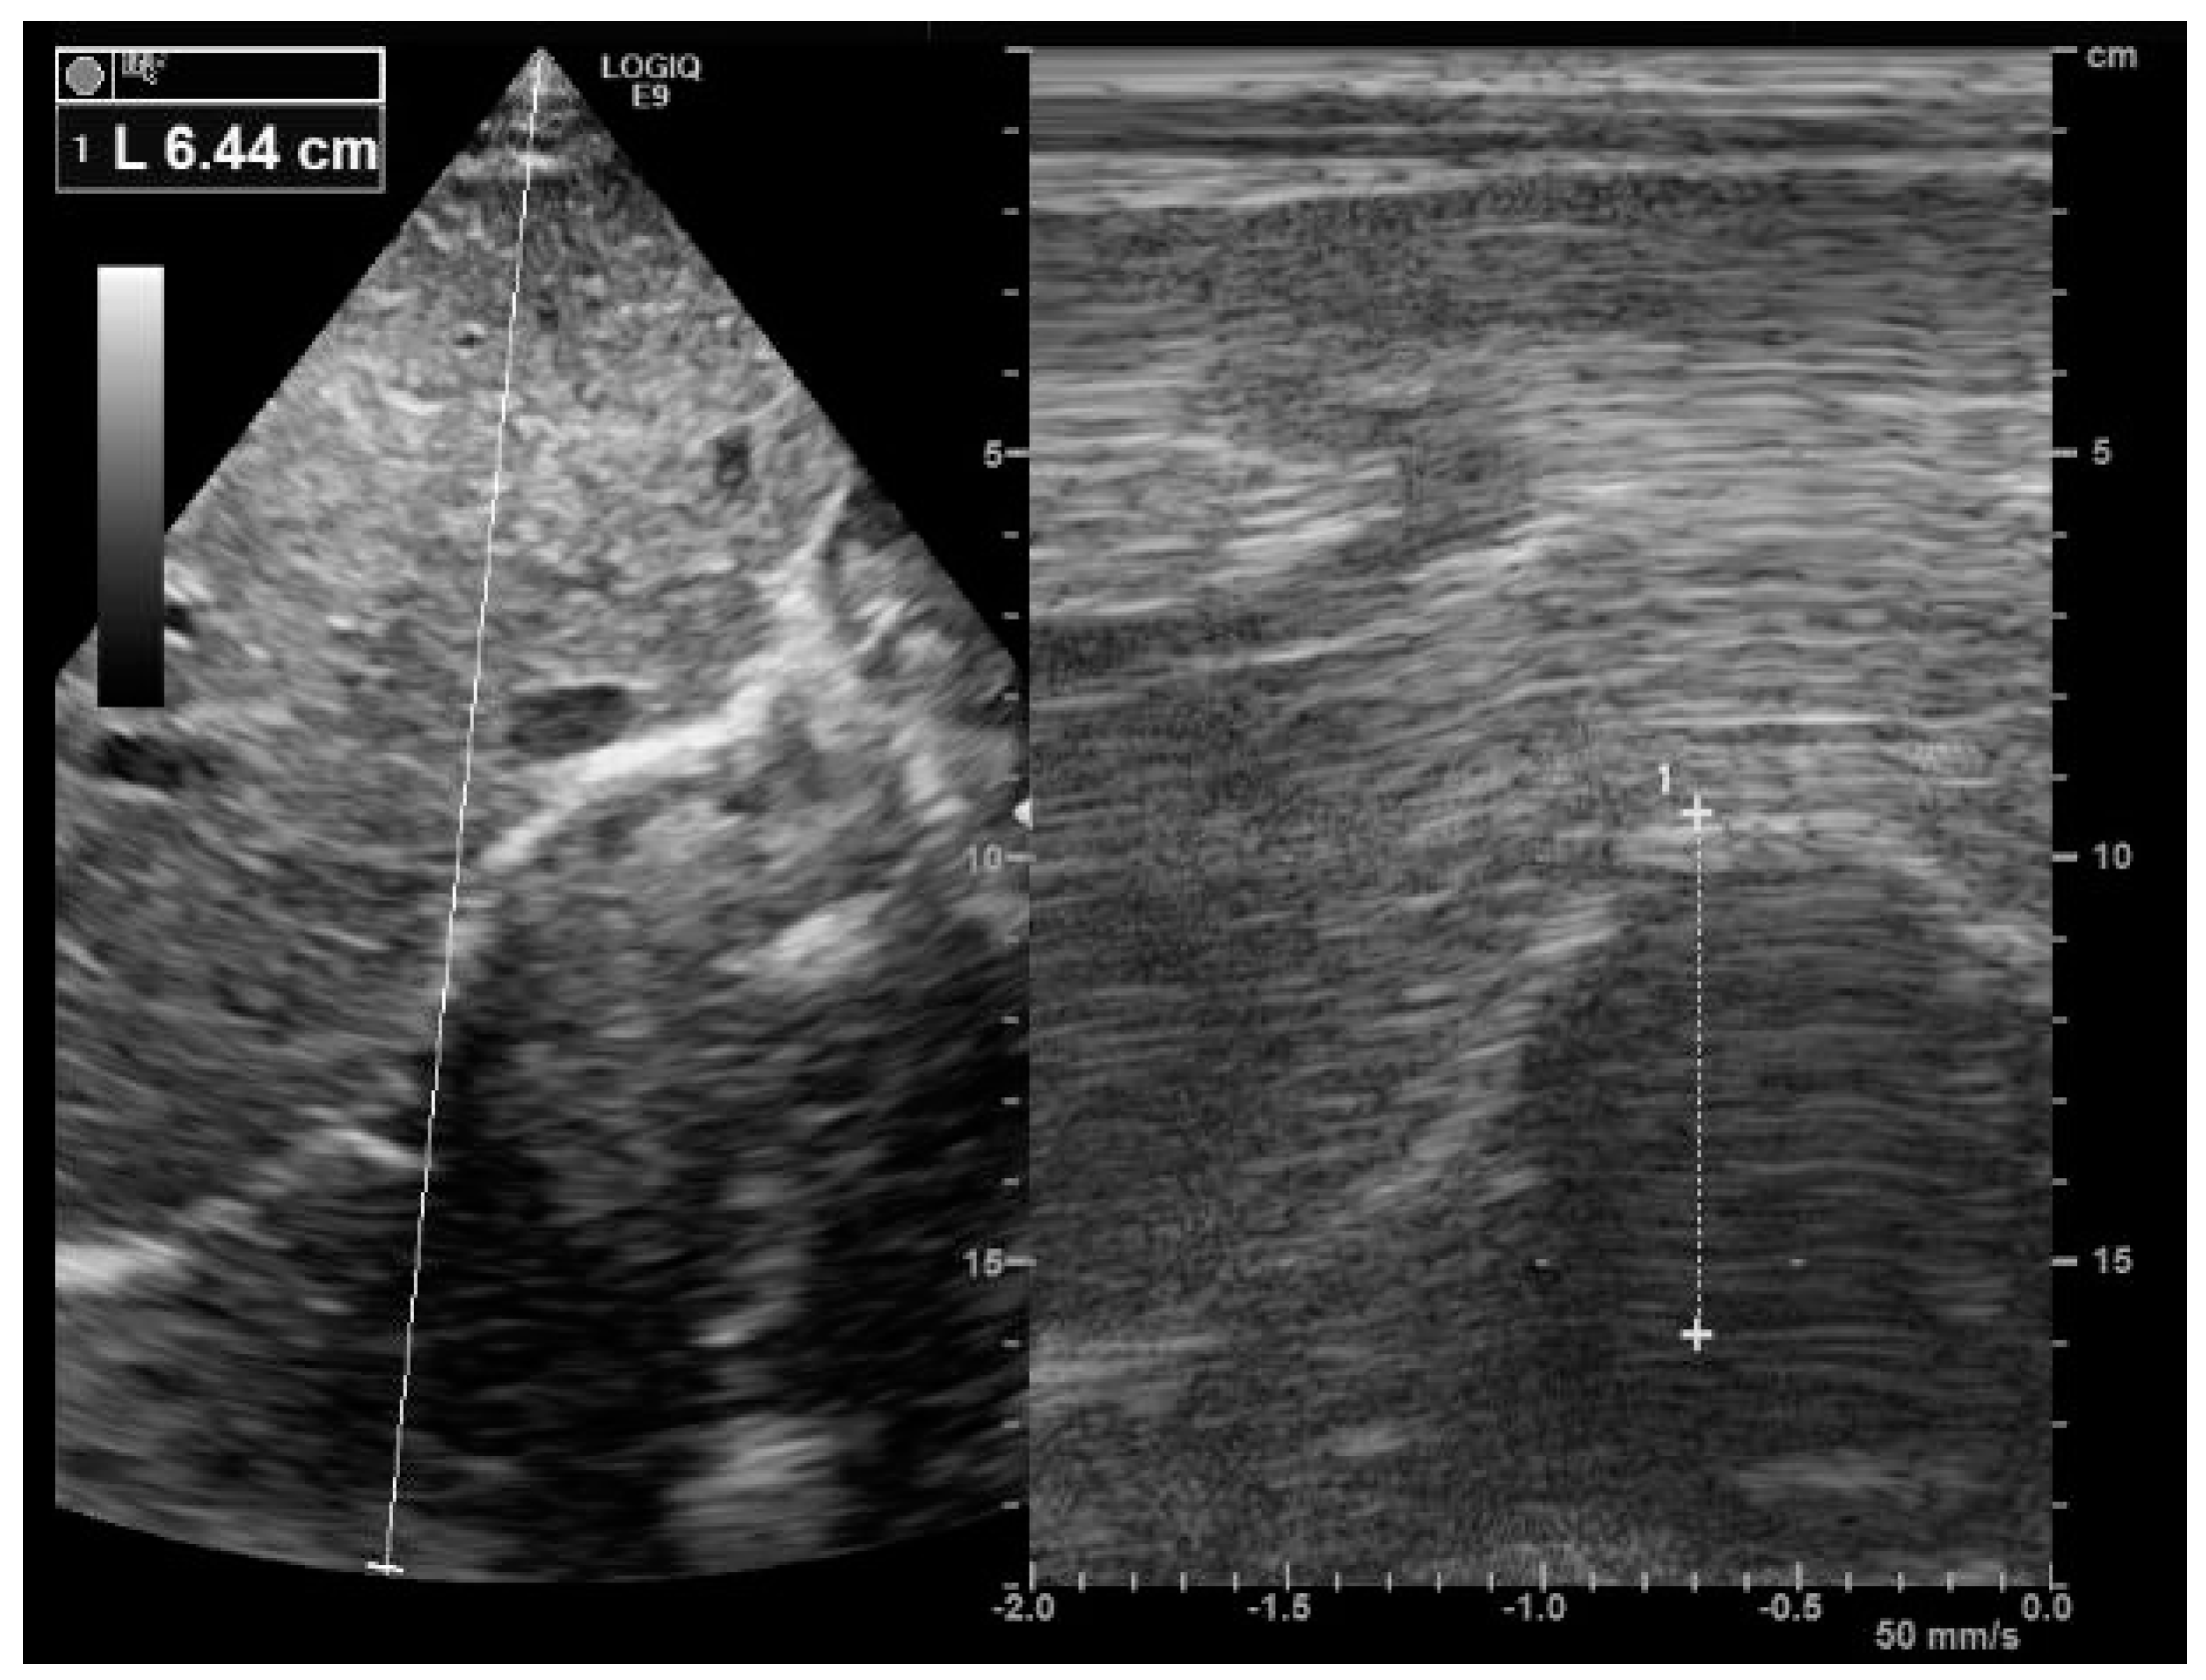

4.1. The Subcostal Approach

- Boussuges, A.; Gole, Y.; Blanc, P. Diaphragmatic motion studied by m-mode ultrasonography: Methods, reproducibility, and normal values. Chest 2009, 135, 391–400. [Google Scholar] [CrossRef]